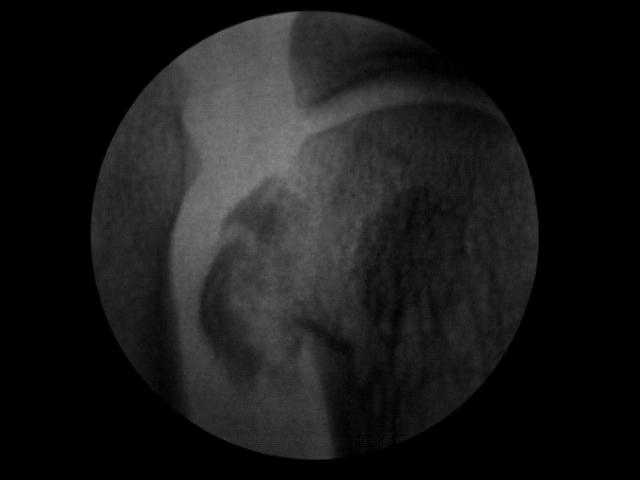

Los sesamoideos son 2 pequeños huesecillos del tamaño de una aceituna que se encuentran bajo la cabeza del primer metatarsiano. Pese a lo pequeños que son tienen una gran papel y función biomecánica en el gesto del despegue en la marcha humana. Estos 2 grandes desconocidos pueden llegar a causar un incapacitante dolor cuando por alguna razón se inflaman dando lugar a una sesamoiditis. El dolor se localiza en la planta del pie justo en la zona prominente que podemos palpar al flexionar el dedo gordo. Este cuadro de dolor se agrava con la deambulación en el gesto del despegue ya que soportan toda la carga de nuestro peso corporal justo en el momento de flexión máxima del dedo gordo.

La sesamoiditis puede ser causada por una fractura de estrés que generalmente es espontánea y debida a una sobrecarga de presión continuada, suele aparecer en personas muy activas y deportistas que soportan grandes fuerzas compresivas sobre el hueso (sesamoideo) el cual finalmente «estalla» provocando la fractura de estrés del mismo. Cabe nombrar que existe una enfermedad degenerativa conocida como osteonecrosis de Renander que consiste en la falta de riego sanguíneo lo cual genera una «muerte» del tejido óseo provocando también la pérdida de función del mismo y dolor intenso. Esta enfermedad suele aparecer en la primeras dos décadas de vida con mayor incidencia en mujeres atletas y bailarinas que ejercen una excesiva dorsiflexión forzada en su acto deportivo.